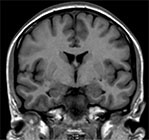

Пример МРТ областей гиппокампа

МРТ областей гиппокампа

На серии FLAIR, Т1- и Т2- взвешенных томограмм головного мозга получены изображения суб- и супратенториальных структур. Выполнено исследование по специальной программе (Ax T2 параллельно сильвиевой борозде и Cor FLAIR перпендикулярно сильвиевой борозде) для оценки височных долей, областей гиппокампа.

Срединные структуры не смещены.

Желудочки обычной формы и размеров. Субарахноидальные пространства не расширены.

Дифференциация серого и белого вещества сохранена. Очаговые изменения в веществе головного мозга не выявлены. Области гиппокампа симметричные с обеих сторон, без очаговых изменений.

МР сигнал от подкорковых ядер не изменен.

Селлярная область без патологических изменений. Размеры гипофиза в пределах нормы.

Стволовые структуры и мозжечок в пределах нормы. Мостомозжечковые углы без особенностей. Краниовертебральный переход не изменен.

Придаточные пазухи и ячейки сосцевидных отростков воздушны. Содержимое глазниц без особенностей.

ЗАКЛЮЧЕНИЕ по снимку МРТ областей гиппокампа: При исследовании без контрастного усиления МР-данных за очаговое поражение вещества головного мозга (в т.ч. областей гиппокампа) не получено.